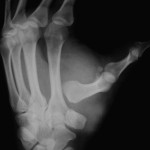

A 54-year-old male presented to the emergency department 5 days after a fall from height, complaining of pain and swelling in his right foot. Initial examination revealed dorsolateral dislocation of the second, third, and fifth MTP joints, coupled with a displaced fracture of the fourth metatarsal neck, while the fourth MTP joint remained intact (Fig. 1). Despite an unsuccessful closed reduction attempt, the patient was scheduled for open reduction and K-wire fixation to address the fourth metatarsal fracture and potentially facilitate the reduction of other MTP dislocations. A dorsal approach with two planned incisions was selected for the procedure. The initial incision was made in the third intermetatarsal space, and a careful dissection was performed to identify and reduce the challenging fourth metatarsal fracture. However, the reduction proved difficult, and satisfactory alignment with K-wires could not be achieved. Consequently, an extension of the incision proximally was required to manipulate the fracture effectively. Subsequently, a dorsal incision in the first intermetatarsal space was made, revealing soft tissue interpositions hindering the reduction of the second MTP joint. Through meticulous dissection and the release of soft tissue interpositions, the reduction of the second MTP joint was facilitated. This, in turn, led to the simultaneous reduction of the other MTP dislocations and the fourth metatarsal fracture. During the procedure, it was noted that the capsule and plantar plate were buttonholed into the joint space. The surgeon carefully pushed the plantar plate and other soft tissues posteriorly while simultaneously applying traction and a medial push to the proximal phalanx. Alternating dorsiflexion and plantar flexion maneuvers were employed at the second MTP joint to aid in the reduction. Importantly, the plantar plate was preserved throughout the procedure. The second MTP joint was stabilized with a K-wire, and under image guidance, confirmation was obtained that all other dislocations were reduced and the fracture was in good alignment. Additional K-wire fixation was extended to stabilize the third MTP joint as well (Fig. 2).